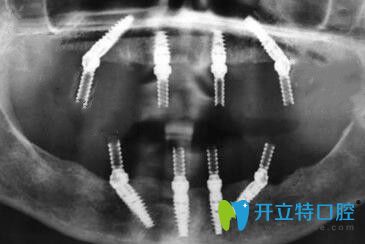

從面診到拍CT片、身體的多種常規(guī)檢查等,一樣不漏;統(tǒng)統(tǒng)做完后才制定修復方案。方醫(yī)生說從各種檢查情況來看,我比較適合做全口ALL-ON-4種植牙,這樣不僅省錢,手術速度快、創(chuàng)傷也很小。

還沒等方醫(yī)生制定完種植方案,我都著急要做種植牙(想盡快長出“新牙”);手術中醫(yī)生的操作手法很輕也很熟練,所以整個種植過程中沒有感覺到明顯的疼痛~~~